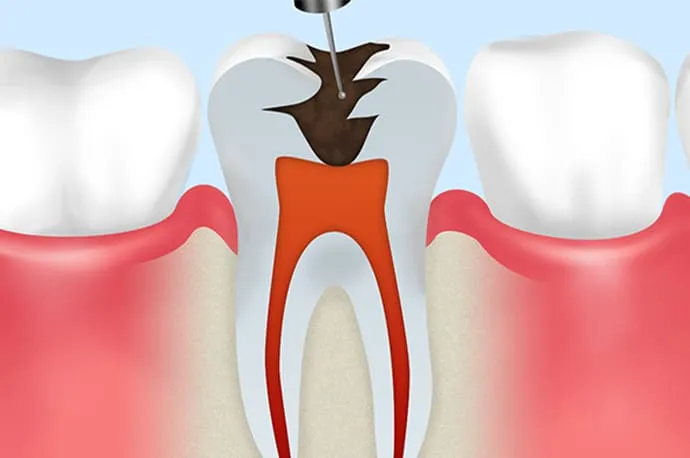

①抜髄

まだ死んでいない歯の神経を取り除く処置を抜髄といいます。虫歯や歯の破折が原因で細菌が歯の神経まで到達し、炎症を起こしている状態(歯髄炎)がこれにあたります。

原因を取り除くことで神経が回復する場合もありますが、炎症の程度によっては、早急に神経を取る必要があるケースもあります。

まだ細菌感染が成立していない段階で行う治療のため、治療の成功率は約90%とされています。